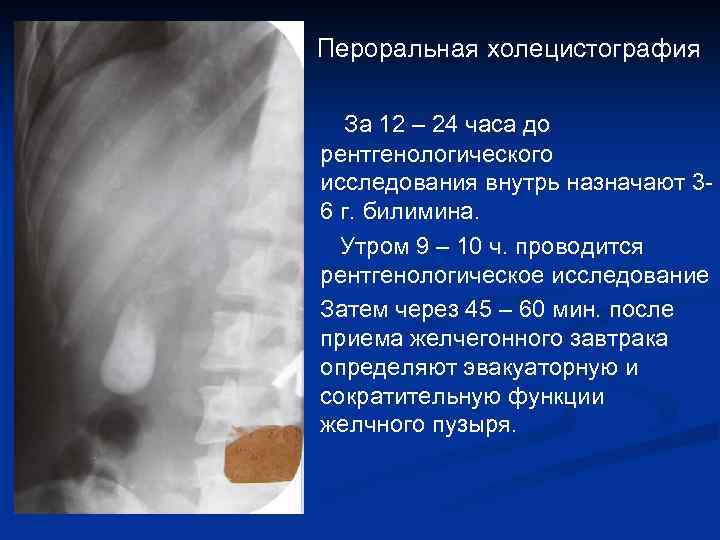

Пероральная холецистография За 12 – 24 часа до рентгенологического исследования внутрь назначают 36 г. билимина. Утром 9 – 10 ч. проводится рентгенологическое исследование Затем через 45 – 60 мин. после приема желчегонного завтрака определяют эвакуаторную и сократительную функции желчного пузыря.

Пероральная холецистография За 12 – 24 часа до рентгенологического исследования внутрь назначают 36 г. билимина. Утром 9 – 10 ч. проводится рентгенологическое исследование Затем через 45 – 60 мин. после приема желчегонного завтрака определяют эвакуаторную и сократительную функции желчного пузыря.